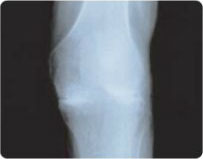

STAGE 3

Subluxation with Deformity